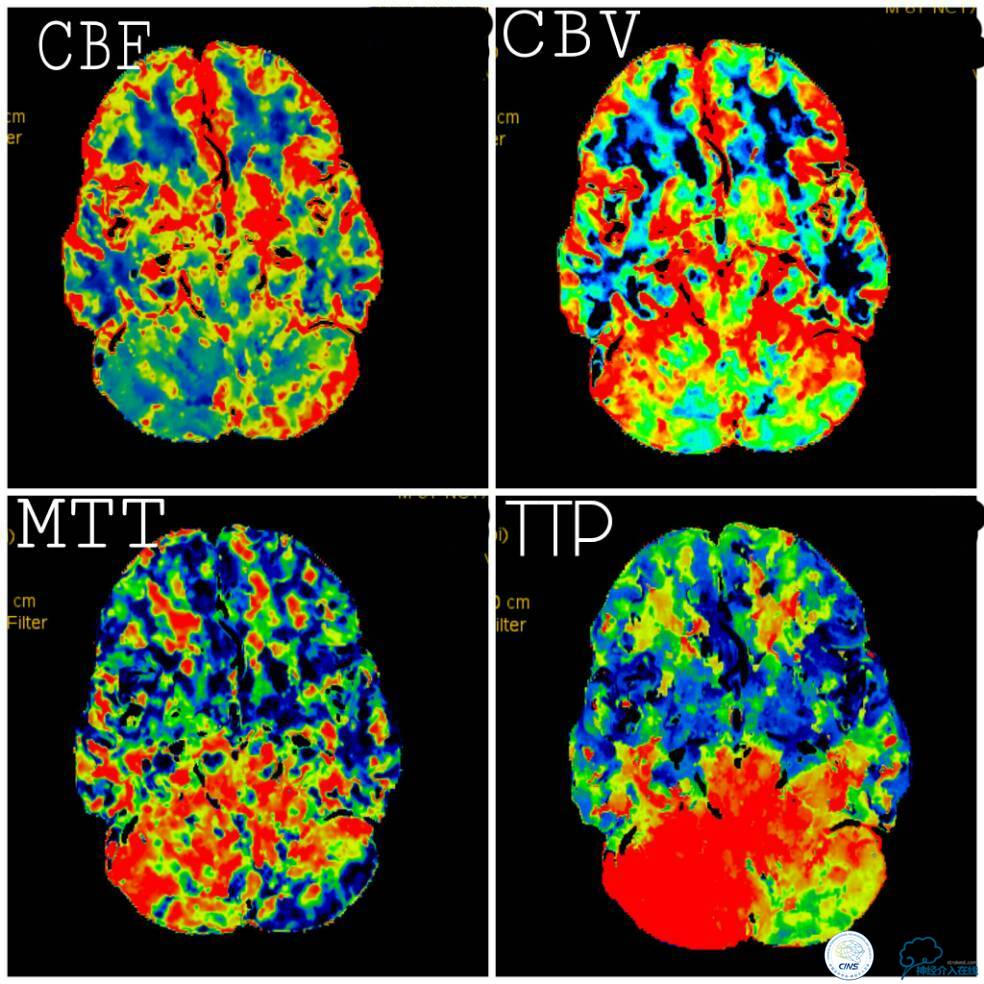

椎基底动脉高分辨核磁提示右椎动脉V4段闭塞,闭塞段管腔内可见高信号(箭头),考虑血栓,左椎动脉V4段至基底汇合处见向心性斑块(三角)(图7)。

图7